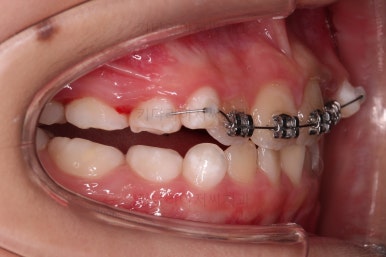

위턱뼈가 가로로 넓어지니 앞니 사이에도 공간이 많이 생겼네요.

부분적으로 교정장치를 부착해서 당사자가 제일 고치고 싶어햇던 앞니 부분을 가지런하게 하기 시작했어요.

위턱뼈가 앞으로도 점점 나와서 처음 보다는 반대교합 경향이 개선되고 있는게 보이네요.

앞니도 굉장히 가지런해졌고요.

반대교합 경항도 거의 없어졌어요.